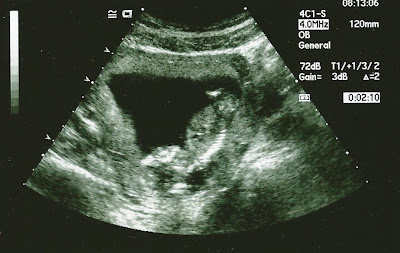

I think one of the best moments of my pregnancy was getting to have a sonogram done in Georgia where the Hubster's Mom used to have her practice. I was about 13 weeks and it was the second time we saw our baby...and it was SO MUCH bigger than the first time!!!

"Hi Everyone!" This baby is already social!!!

Such a sweet little body!!! :-)